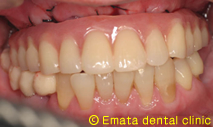

治療後

仮歯までいれるのに半日かかりましたが、患者様には大変喜んでいただきました。